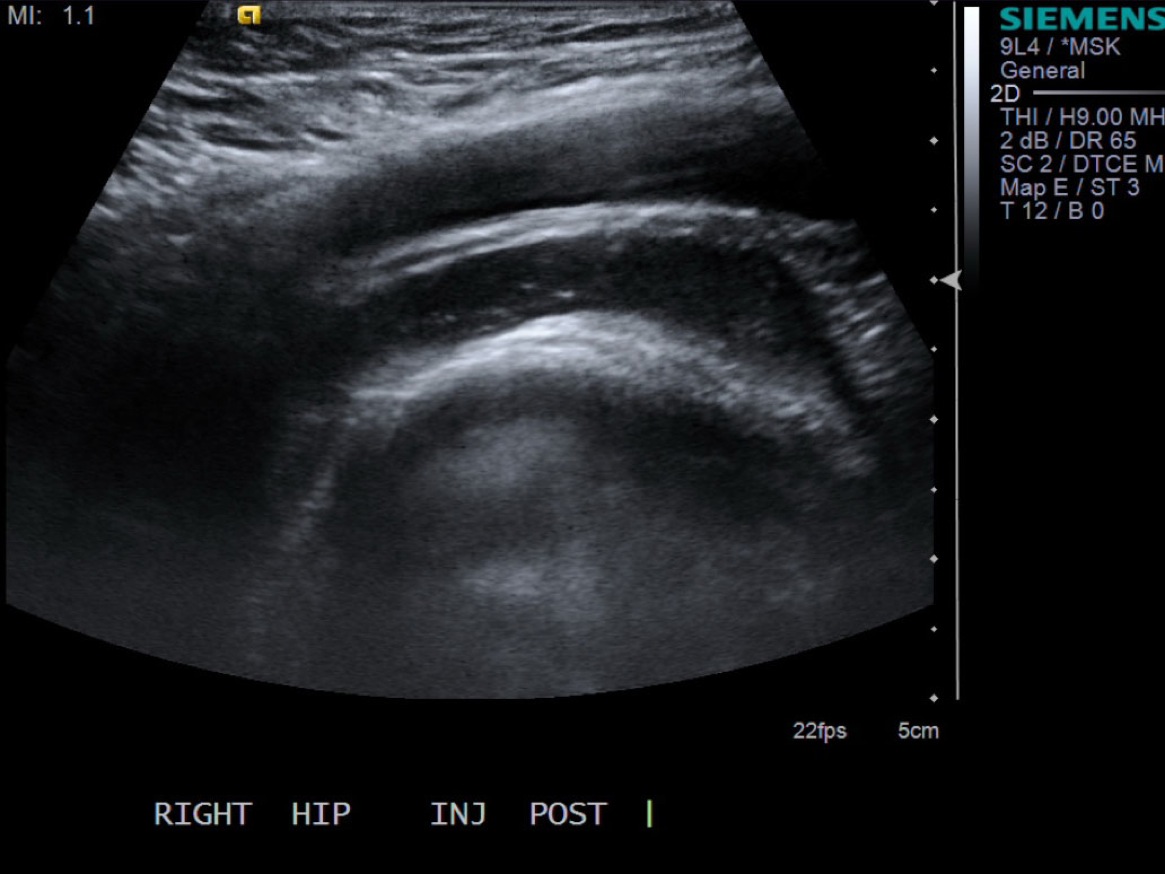

10. Test inject to see if easy flow with 1% lidocaine. If no resistance and see distention of the tendon sheath, exchange for 5cc syringe with injectable steroid and ropivacaine.

12. Scan joint to demonstrate distention. Can try to flex hip to see if fluid distended.

• descriptiondescription